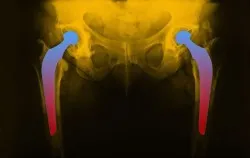

hip-implant-lawsuitAn Arkansas man recently filed a metal hip replacement lawsuit against Biomet, alleging that the company’s M2a-38 Hip Replacement System was defective and harmful.

The plaintiff underwent a total hip replacement in February 2008. He was implanted with a Biomet M2a-38 device, which is a metal-on-metal device.